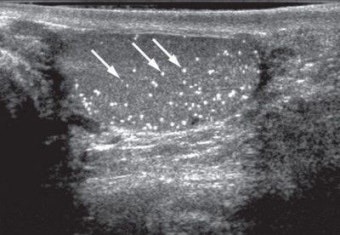

고환암은 남성 생식기관인 고환에 발생하는 악성 종양으로, 초기에는 대부분 통증이 없는 것이 특징입니다. 가장 흔히 보고되는 증상은 한쪽 고환에 단단하게 만져지는 결절(혹)이나 덩어리가 느껴진다는 점입니다. 이런 덩어리는 대체로 시간이 흐르면서 점차적으로 커지는 경향이 있으며, 만졌을 때 통증 없이 딱딱하고 경계가 뚜렷한 특징을 보입니다.

고환의 크기 변화도 주요 초기 징후 중 하나입니다. 급격하게 커지거나 붓는 느낌, 혹은 비대칭적인 크기 차이가 나타날 수 있습니다. 이는 내부 비정상적인 세포 증식이나 체액 저류로 인해 발생하며, 염증이 아닌 암에 의한 변화일 수 있으므로 반드시 주의해야 합니다.

또한 고환의 질감 변화 역시 중요한 신호입니다. 원래는 부드럽고 탄력 있는 조직이던 고환이 암의 진행에 따라 전체적으로 단단하게 느껴질 수 있습니다. 자가검진을 통해 평소와 달리 단단해졌음을 느꼈다면 병원을 방문할 필요가 있습니다.